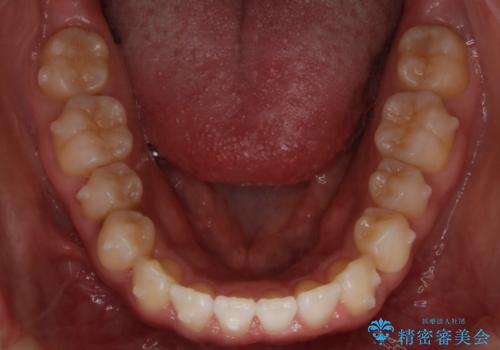

インビザライン矯正 前歯のすきっ歯を治したい

- 上顎の前歯のすきっ歯を治したいとのことで来院されました。

前歯の隙間を閉じる矯正治療の場合、インビザライン適用症例のためインビザラインによる治療をご提案しました。

後戻り防止のため、上唇小帯切除も併用しています。

上唇と歯ぐきを結ぶひも(上唇小帯)が長いと、前歯に隙間が空いてしまうことがあります。今回は隙間を確実に閉じる目的、また矯正後に再び隙間が空かないように、上唇小帯の切除も行っています。